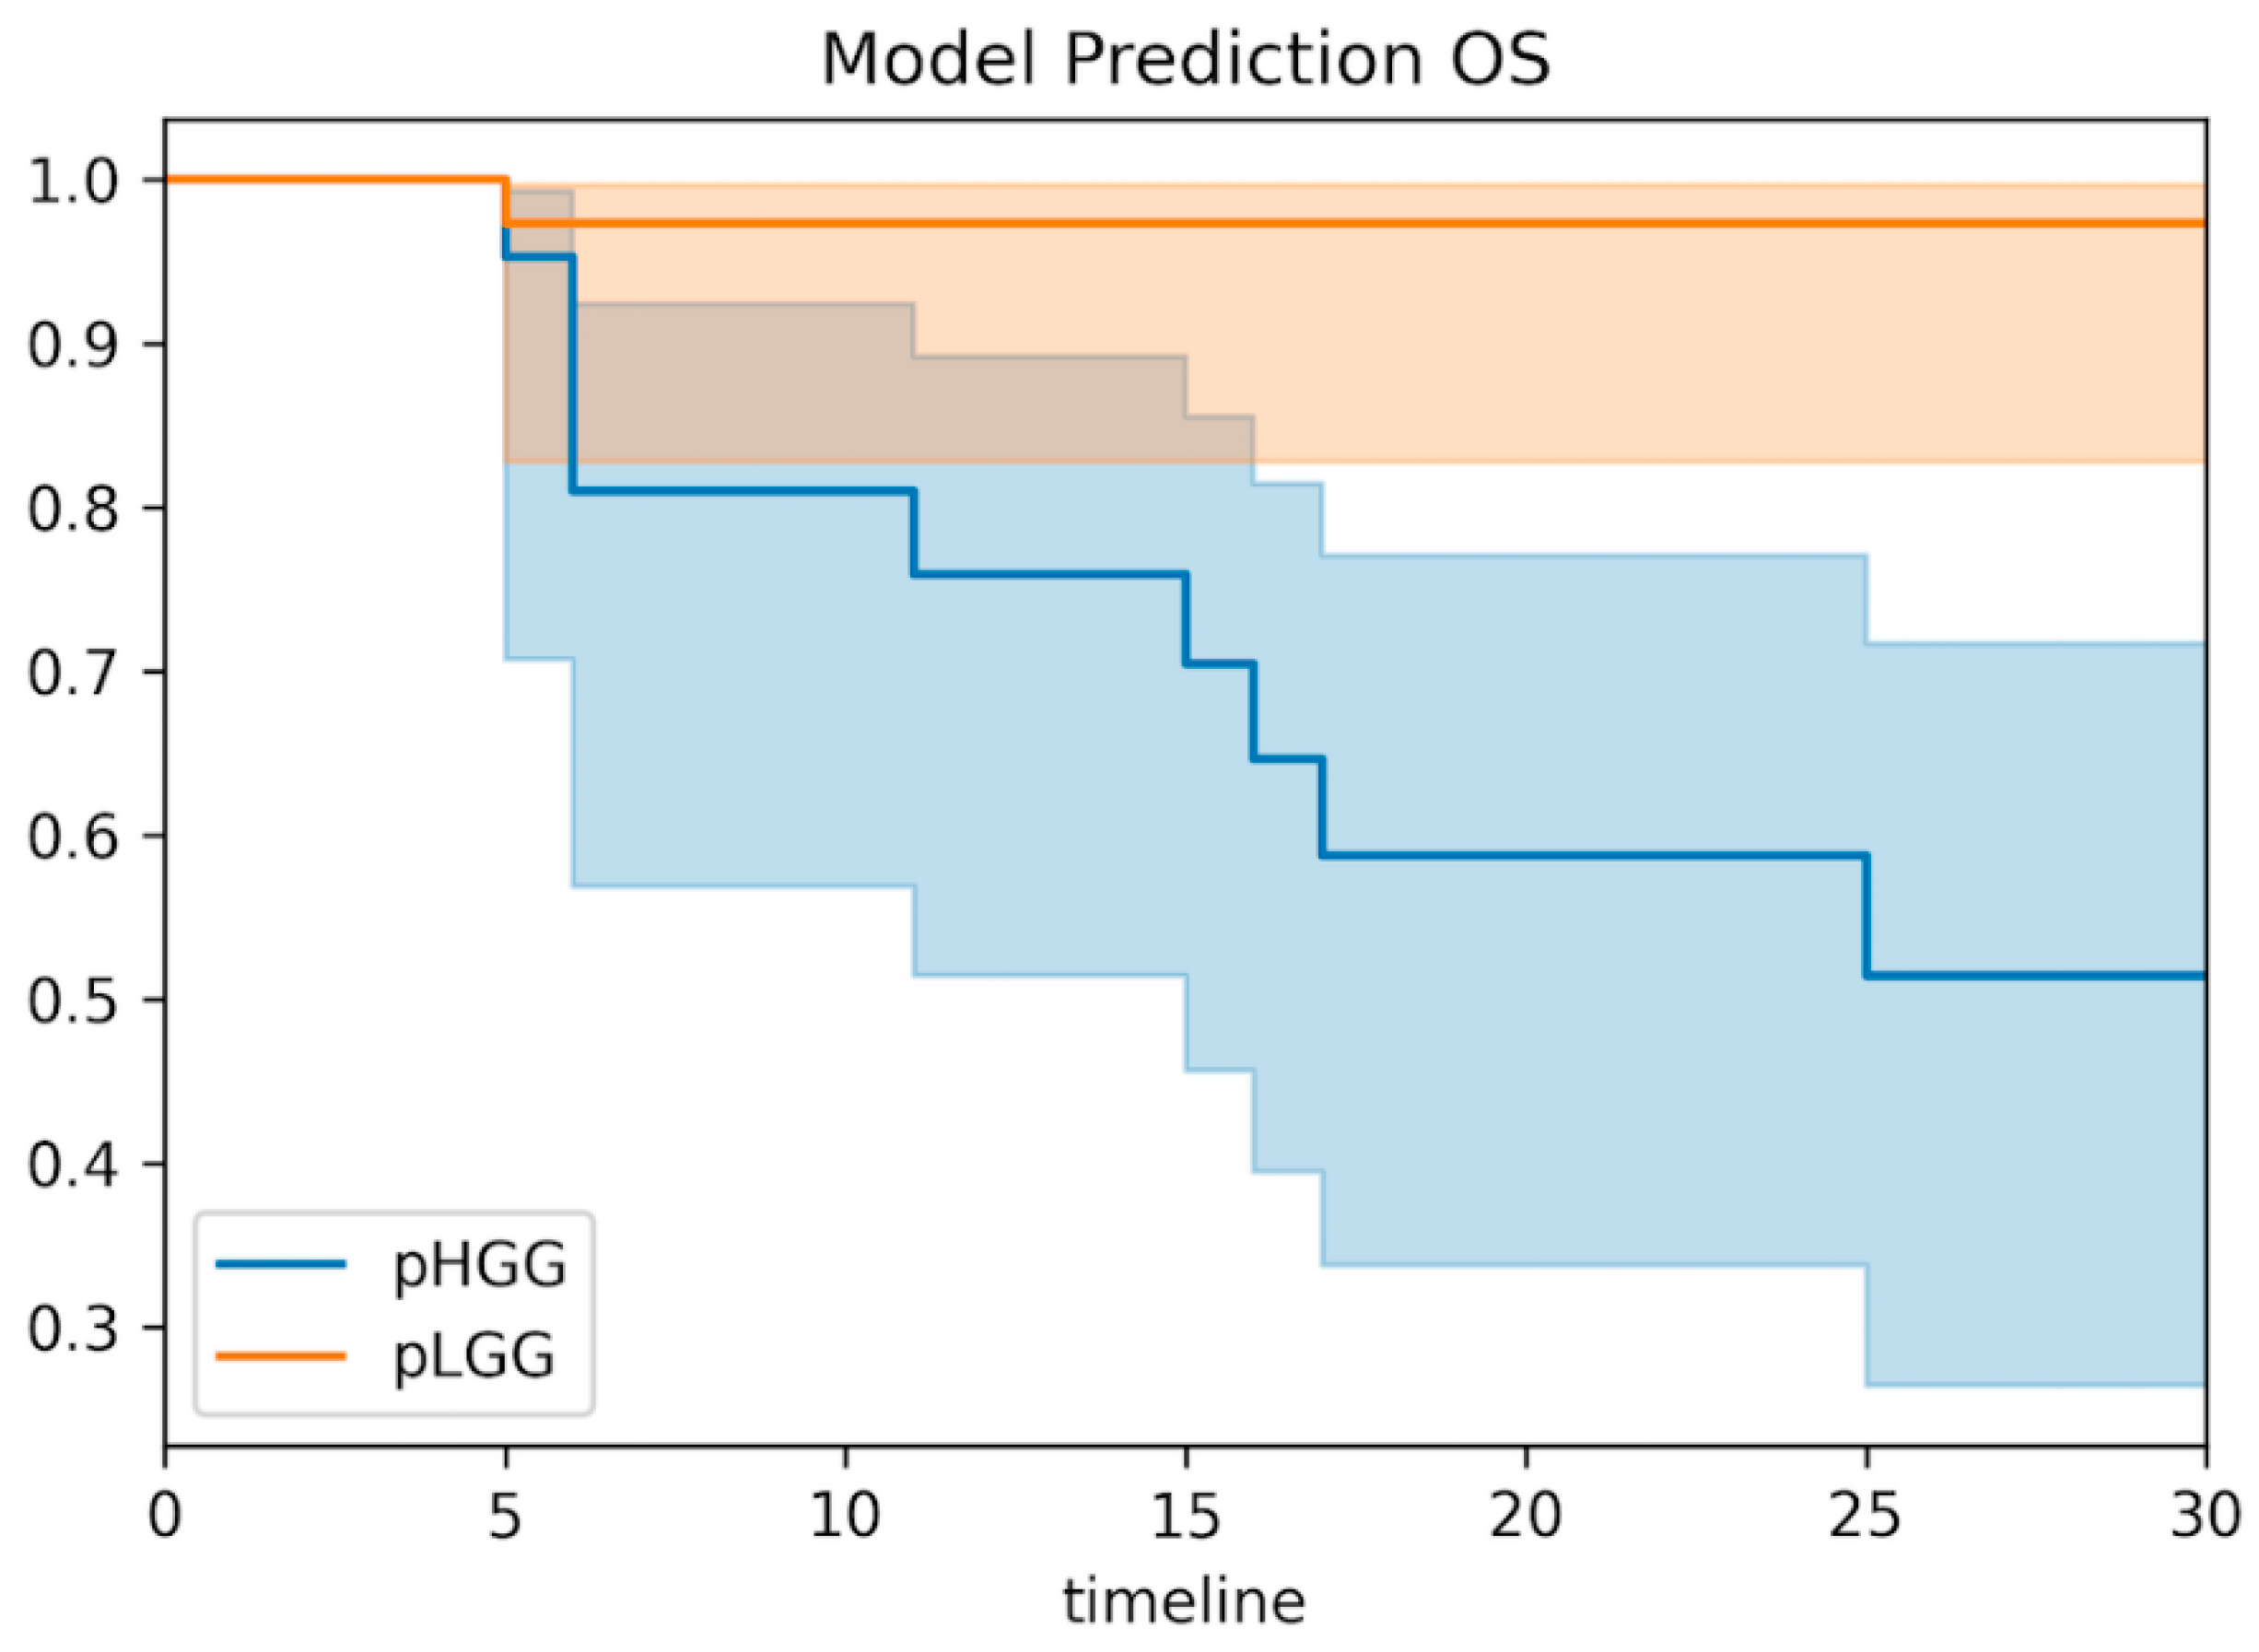

3.6. Clinical Correlations of the Predictive Model